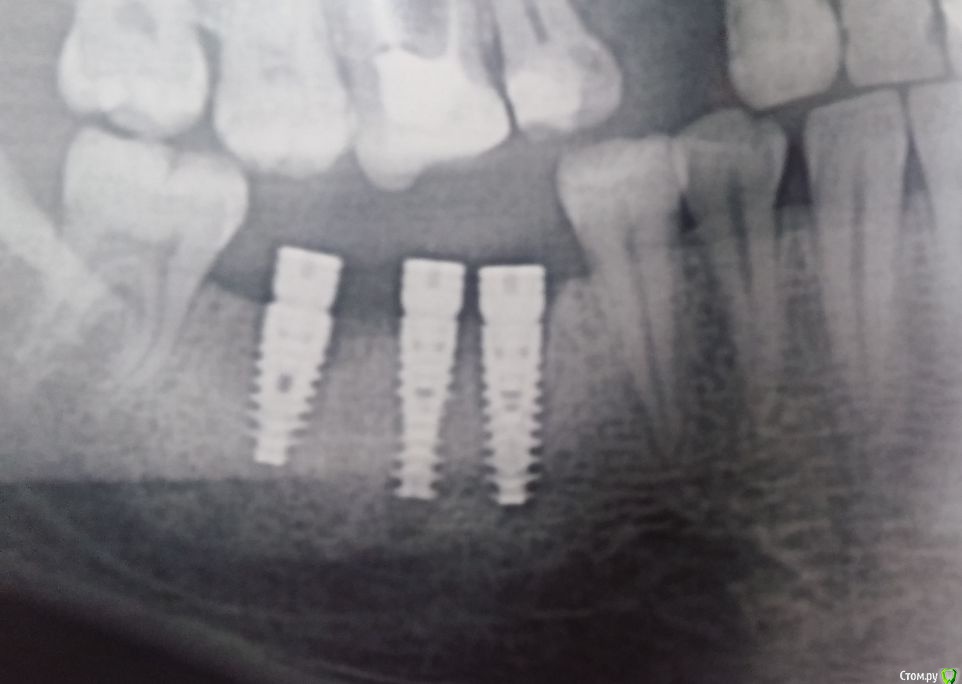

alezx Опубликовано 20 ноября, 2015 Поделиться Опубликовано 20 ноября, 2015 Всем доброго дня. Достаточно давно мне удалили 5 зубов. 9 ноября мне удалили ещё 4 зуба и поставили 8 имплантатов (альфа-био). Удаление и имплантирование прошло одномоментно. К сожалению, я ещё не делал снимок или КТ после имплантации, поэтому схематично могу показать что и где менялось на старых снимках + приложу фото там, где имплантаты видны.Комментарии к снимку:1. Удален зуб, установлен имплантат2. Удалены 2 зуба, установлены 3 имплантат с формирователями3. Удален зуб, установлен имптантат4. Установлены 3 имплантата без формирователя Все обычные последствия прошли достаточно быстро. Отек сошел к концу недели (через 5-6 дней). Болей как таковых не было, кроме первых дней и все казалось бы шло, как по маслу. Но примерно с 15 числа появилась глубокая (не знаю как верно это назвать, то есть она была не сильной и как будто где-то в глубине кости) боль с правой стороны нижней челюсти. Решив, что это просто часть последствий после тяжелой операции принял кетанов и постарался не обращать внимание. На следующий день все повторилось, к вечеру боль вернулась. И так начало повторяться каждый день.Вчера, 19 числа, я снимал швы (у другого врача) и решил проконсультироваться по поводу боли. Мне озвучили, что это вполне нормально и должно скоро пройти.Вечером кетанов решил, что хватит с меня и действовать перестал. Боль уже добралась звоном до уха. Ночь прошла интересно. В 5 утра я выпил нимесил и тогда смог уснуть. В это время боль уже отдавала в крайних нижних зубах при надавливании на них + немного побаливало с левой стороны челюсти (там уже все заросло десной и до этого времени не беспокоило). Разумеется судьба привела меня сюда и судя по прочитанному из других тем, боль на 10 день после операции - это совсем не нормально (успокойте меня, если ошибаюсь).Мысли тревожат вариантами "не прижились имплантаты" или "задет нерв", хотя второе сомнительно, ведь у меня не было онемения.. Хотелось бы услышать ваши мысли по поводу происходящего со мной. Так же уточню:1. Снимок сделаю, вопрос только в его срочности (бежать прямо сейчас с работы или можно подождать начала следующей недели?)2. К сожалению, наблюдаться дальше у того же хирурга, что делал операцию я не могу. Планировал протезироваться в одной из клиник города, но ещё не выбрал в какой. Вариант обращаться даже за переделкой сделаного в то же учреждение - крайний для меня.3. О состоянии 8-рки в курсе, стоматологию планировал после этой операции. (Опять же, на форуме прочел, что пишут об обратном (лечение-удаление-имплантация), но на момент косультации со стоматлогом было озвучено "Удаляй все, потом приходи". Только вот не знаю, приходить ли к нему...) Ссылка на комментарий

alezx Опубликовано 25 ноября, 2015 Автор Поделиться Опубликовано 25 ноября, 2015 Сделал снимок. Надеюсь качество удобоваримое. Про боли - продолжаются, ближе к вечеру. Не регулярно. За все дни только вчера не выдержал и принял кетанов, до этого было терпимо, хоть и дискомфортно. Есть мысль о том, что это из-за еды. Может быть зря я перешел на относительно твердую пищу (картофельное пюре, супы с овощами) и нужно было продолжать детское питание и йогурты из трубочки? Десна все ещё не зажила со стороны, где имплантаты с формирователями, между ними небольшая бороздка (попадание горячего-холодного-любого в неё могло спровоцировать?) Ссылка на комментарий

Vitasem Опубликовано 28 ноября, 2015 Поделиться Опубликовано 28 ноября, 2015 Вполне возможно пульпит в 8ке - на первом снимке видна под эмалью полость, хотя на двух других не очень видна.Да и по смптомам(боли ночью) больше смахивает на пульпитВизуальный осмотр, препарирование 8го для исключения его как источника боли.Может еще и формирователь в 1м импланте в области 46 поджимать кость.Пока по теперешним рекомендациям пополощите рот р-ром хлоргексидина 0,5%.Почистили зубы и набрали 1 стол ложку и 2-3 минуты пополоскали.ПС. Через месяц - два - нежно будет проверить жизнеспособность 13, если нерв погиб - эндодонтия. (верхушка импланта рядом с верхушкой 13. Ссылка на комментарий